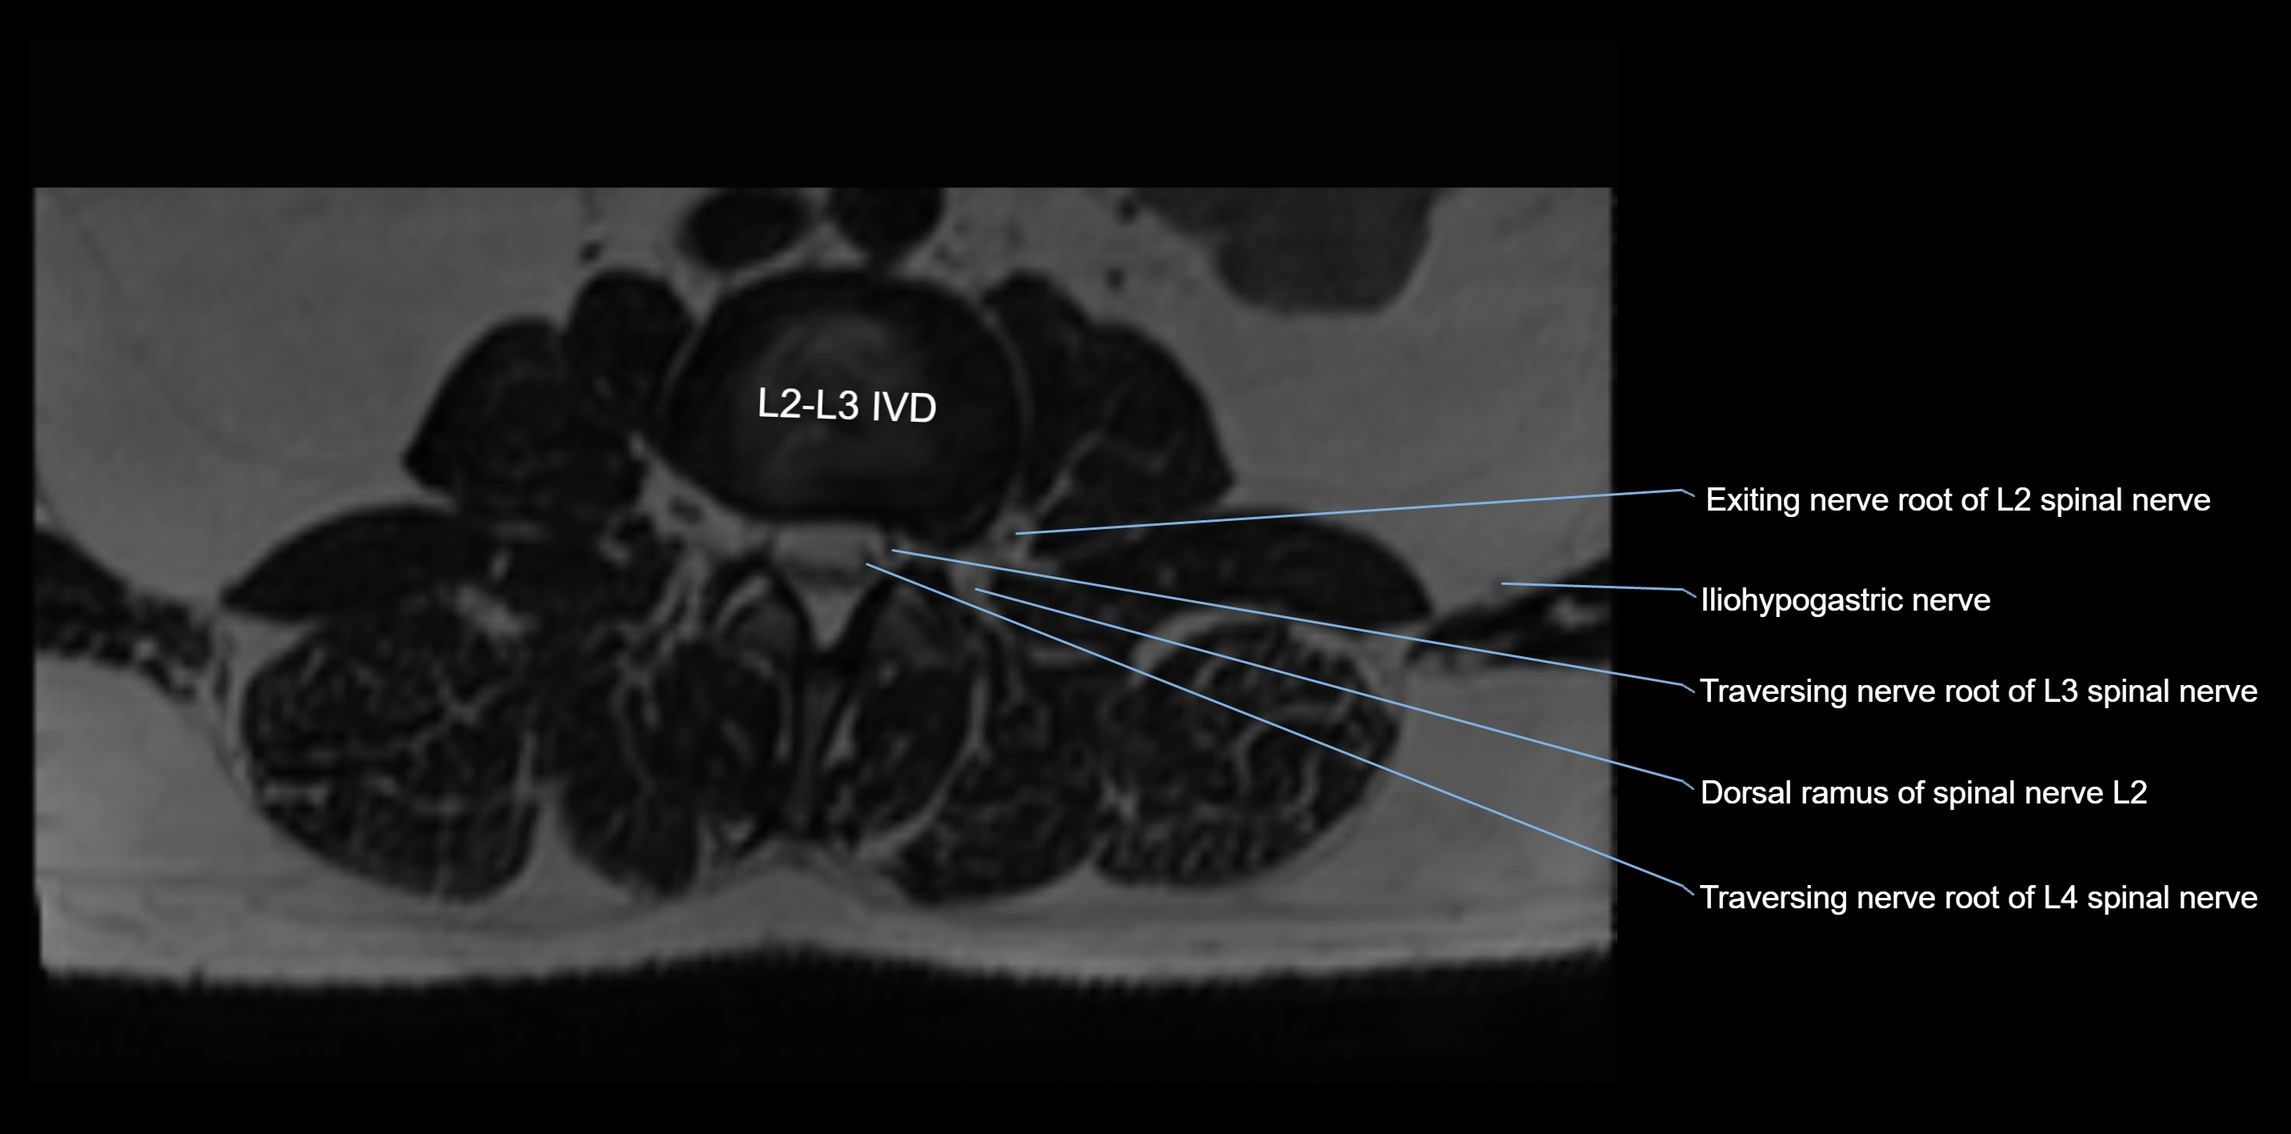

MRI Appearance

T1-weighted images:

• Nerve appears as a very thin low-to-intermediate signal intensity structure

• Surrounded by bright fat, aiding visualization

T2-weighted images:

• Nerve shows intermediate to mildly hyperintense signal compared to muscle

• Pathological involvement appears brighter

STIR (Short Tau Inversion Recovery):

• Normal nerve appears dark

• Inflamed or entrapped nerve appears bright hyperintense

T1 Fat-Sat Post-Contrast:

• Normal nerve enhances minimally

• Pathologic nerve (neuritis, entrapment, tumor infiltration) shows focal or diffuse enhancement

3D T2 SPACE / CISS:

• Nerve appears intermediate to mildly hyperintense compared to muscle

• Surrounded by bright fat or CSF, improving visualization

• Best sequence for mapping small pelvic nerves such as the anococcygeal